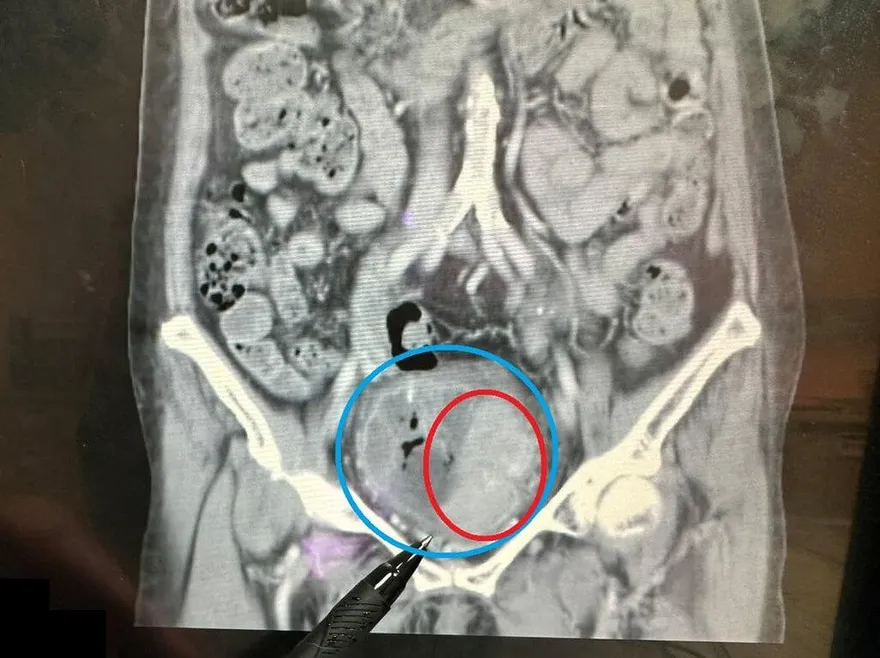

大腸鏡檢查

膀胱大腸相通

陳榮堅醫師

腹腔鏡手術

尿液感染

肛門滲漏

膀胱壁破裂